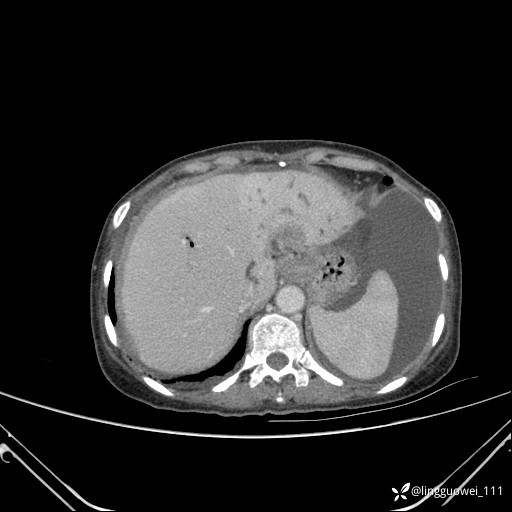

病例女,65岁,门诊行胃肠镜检查后,说腹胀入院检查,CT能发现病因吗?已公布结果

主诉:门诊行胃肠镜检查后,诉腹胀,入院检查,肝有病变吗?腹膜及腹腔的表现有特征性吗?

门脉期: